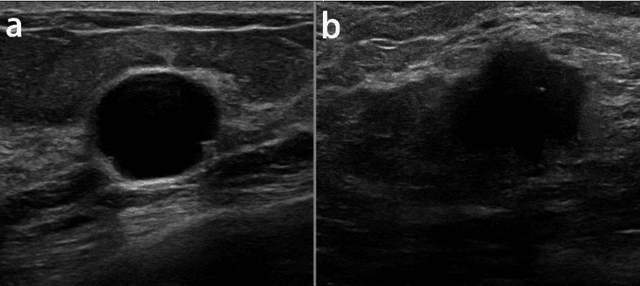

Abstract:Reliable classification of benign and malignant lesions in breast ultrasound images can provide an effective and relatively low cost method for early diagnosis of breast cancer. The accuracy of the diagnosis is however highly dependent on the quality of the ultrasound systems and the experience of the users (radiologists). The leverage in deep convolutional neural network approaches provided solutions in efficient analysis of breast ultrasound images. In this study, we proposed a new framework for classification of breast cancer lesions by use of an attention module in modified VGG16 architecture. We also proposed new ensembled loss function which is the combination of binary cross-entropy and logarithm of the hyperbolic cosine loss to improve the model discrepancy between classified lesions and its labels. Networks trained from pretrained ImageNet weights, and subsequently fine-tuned with ultrasound datasets. The proposed model in this study outperformed other modified VGG16 architectures with the accuracy of 93% and also the results are competitive with other state of the art frameworks for classification of breast cancer lesions. In this study, we employed transfer learning approaches with the pre-trained VGG16 architecture. Different CNN models for classification task were trained to predict benign or malignant lesions in breast ultrasound images. Our Experimental results show that the choice of loss function is highly important in classification task and by adding an attention block we could empower the performance our model.